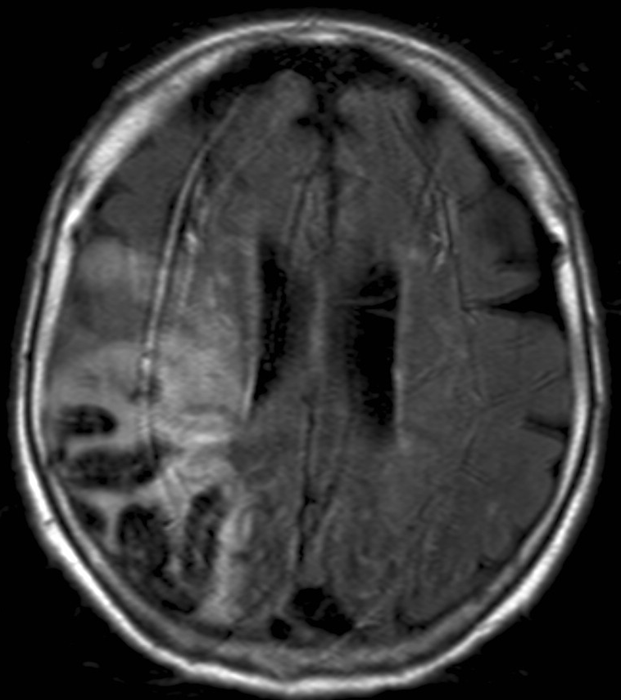

All three types of intracranial hematoma can occur as a result of head trauma:

• Rupture of the meningeal arteries may give rise to an epidural hematoma. At the site of the hematoma skull fracture can be observed.

4.Middle-aged man some days after direct head trauma. On noncontrast CT a lens-shaped, slightly inhomogenous epidural hematoma can be seen, that causes compression of the right lateral ventricle (left panel). In bone window skull fracture without dislocation can be found at the site of the hematoma (right panel).

• Subdural bleeding is caused by injured bridging veins (elongation, tears) e.g. when a sudden deceleration occurs. This type of injury generally is not associated with a fracture.

5. A middle aged chronic alcoholic male. On unenhanced CT a typical crescent shape subdural hemorrhage is seen on both sides. Because of its etiology it extends across suture lines.

• Contusion hemorrhage occurs upon sudden deceleration (e.g. car accident - collision) when the brain parenchyma due to its inertness keeps moving and hits the cranial bone. Frequently, contusion develops on the opposite side as well, since on an abrupt stop the brain collides with the bone than bounces off and hits the opposite wall of the skull. (coup - contrecoup effect)

7. Elderly female was suffered a direct hit in the parietal region. Coronal reconstruction of a unenhanced CT scan: At the site of the impact on the right side parietally a typical lens shaped epidural hematome is formed. On the opposite side in the temporal lobe at the contrecoup contusion site parenchymal bleeding is seen